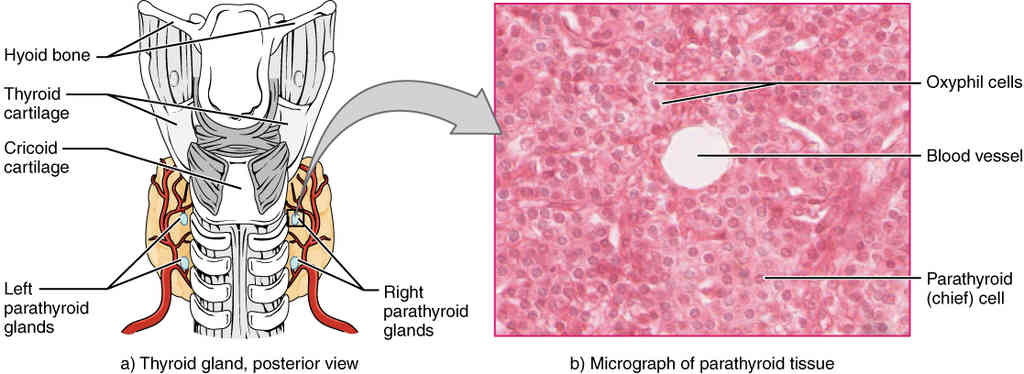

This page is under construction. For now, it is just a resource of the images found in the OpenStax Anatomy and Physiology Handbook. It wil slowly change into a revision tool. Each slide has a number. Use this to refer to the slide. When completed, it will have an unlabelled section, with labelled slides in parallel. On the unlabelled slides, write your answer and use the labelled slide to assess yourself. Keep track by also noting the number on each slide. Improvement at each attempt is important, more so than full marks on a first attempt.